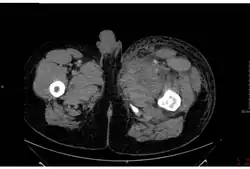

Отёк и некроз в тканях большой приводящей мышцы на КТ при септической форме заболевания

Септическая форма встречается довольно редко. Заболевание начинается остро с озноба и повышения температуры до +39…+40 °C. Наблюдаются выраженные тахикардия, одышка, тахипноэ, боли в груди и кашель с выделением пенистой кровянистой мокроты. Определяются признаки пневмонии и плеврального выпота. При развитии инфекционно-токсического шока возникает геморрагический отёк лёгких. В крови и мокроте обнаруживают большое количество сибиреязвенных бактерий. У части больных появляются боли в животе, присоединяются тошнота, кровавая рвота, жидкий кровянистый стул. В последующем развивается парез кишечника, возможен перитонит. Обнаруживаются симптомы менингоэнцефалита. Инфекционно-токсический шок, отёк и набухание головного мозга, желудочно-кишечное кровотечение и перитонит могут явиться причиной летального исхода уже в первые дни заболевания.